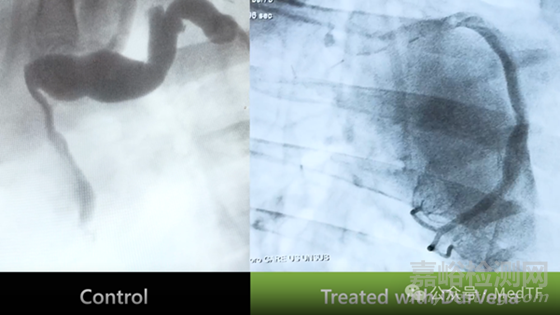

PTP交聯(lián)橋血管效果

通過動物試驗(yàn)可以明顯看到,沒有使用PTP的橋血管變得迂曲、擴(kuò)張,導(dǎo)致血液流動不暢,而PTP技術(shù)處理的橋血管擴(kuò)張非常小,能夠保持血管暢通。